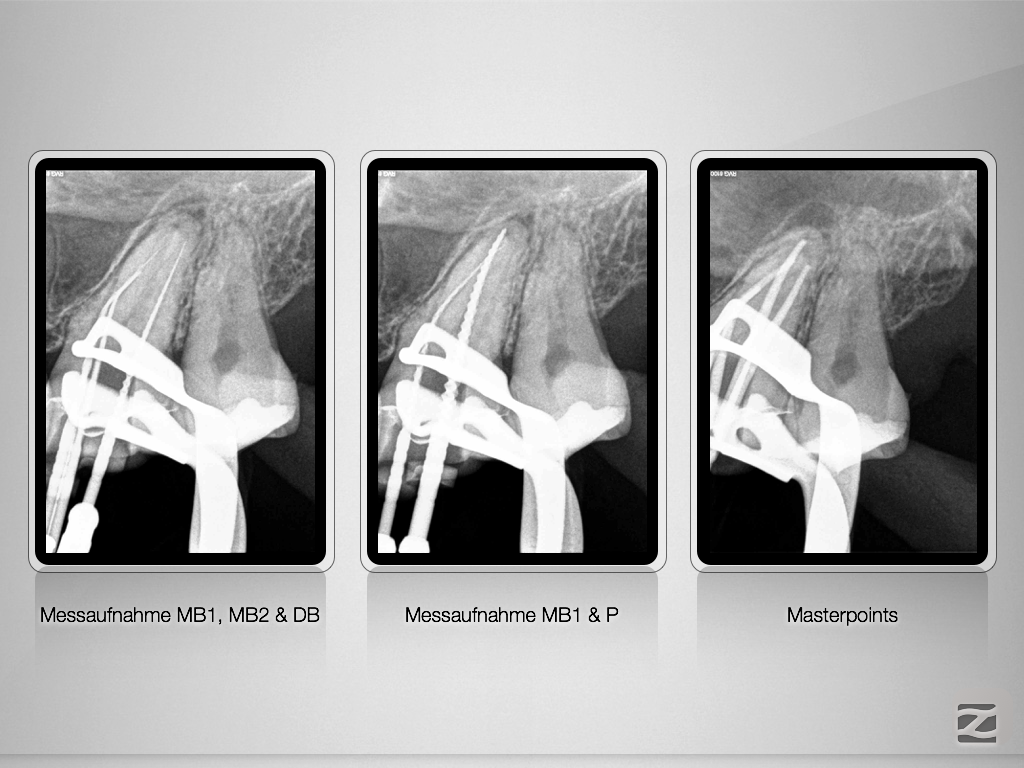

Vitales Gewebe – apikale Aufhellung